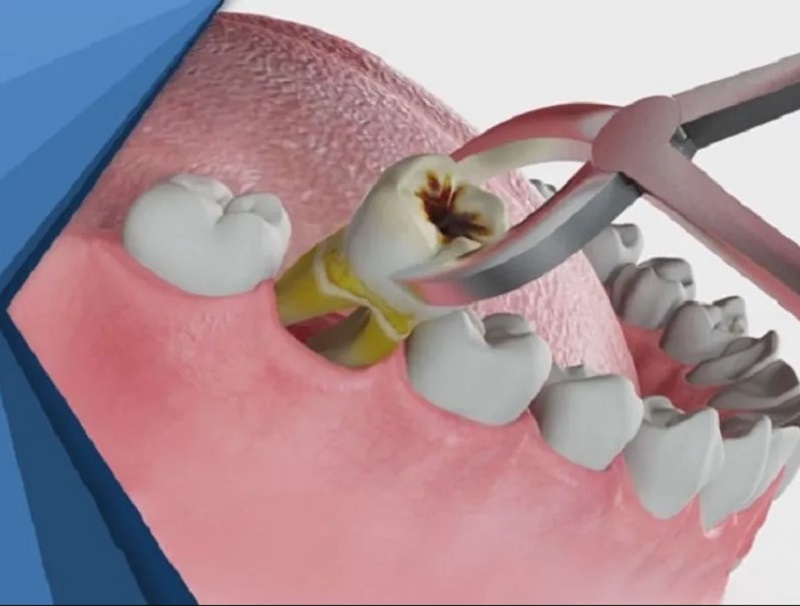

1. Nhổ răng cấm không trồng lại có sao không? 4 hậu quả thường gặp

Mất răng cấm không được phục hồi sớm sẽ khiến răng xô lệch, xương hàm tiêu nhanh, khớp cắn mất cân bằng và răng đối diện trồi xuống, từ đó làm giảm chức năng nhai và gây khó khăn cho việc trồng răng về sau.

1.1 Răng bên cạnh nghiêng đổ vào khoảng trống

Răng cấm giúp giữ ổn định vị trí các răng xung quanh. Khi thiếu răng, khoảng trống tạo ra khiến răng hai bên tự nhiên nghiêng vào, gây lệch vị trí răng, chen chúc, khó vệ sinh, tăng nguy cơ sâu răng, viêm nướu và làm mất thẩm mỹ cung hàm.

1.2 Xương hàm tiêu dần

Khoảng 3–6 tháng sau khi mất răng, xương hàm bắt đầu teo lại do không còn chịu lực nhai, khiến xương hõm xuống, kém săn chắc, ảnh hưởng cấu trúc gương mặt, gây khó cấy Implant và có thể phải ghép xương.